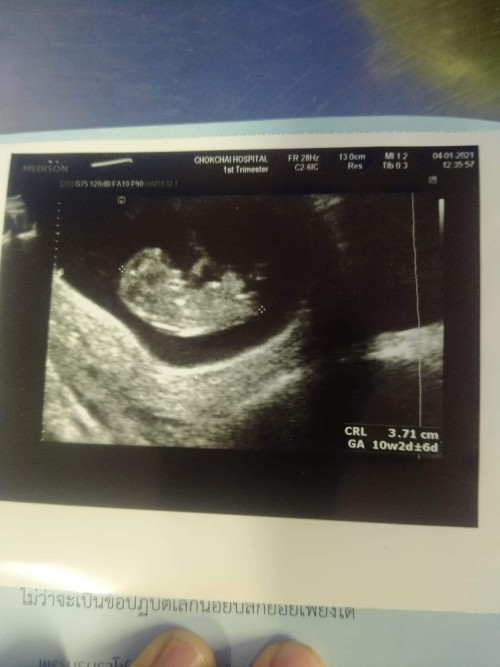

11w2dค่ะตอนนี้18wแล้ว

ตอน10วีคจ้า